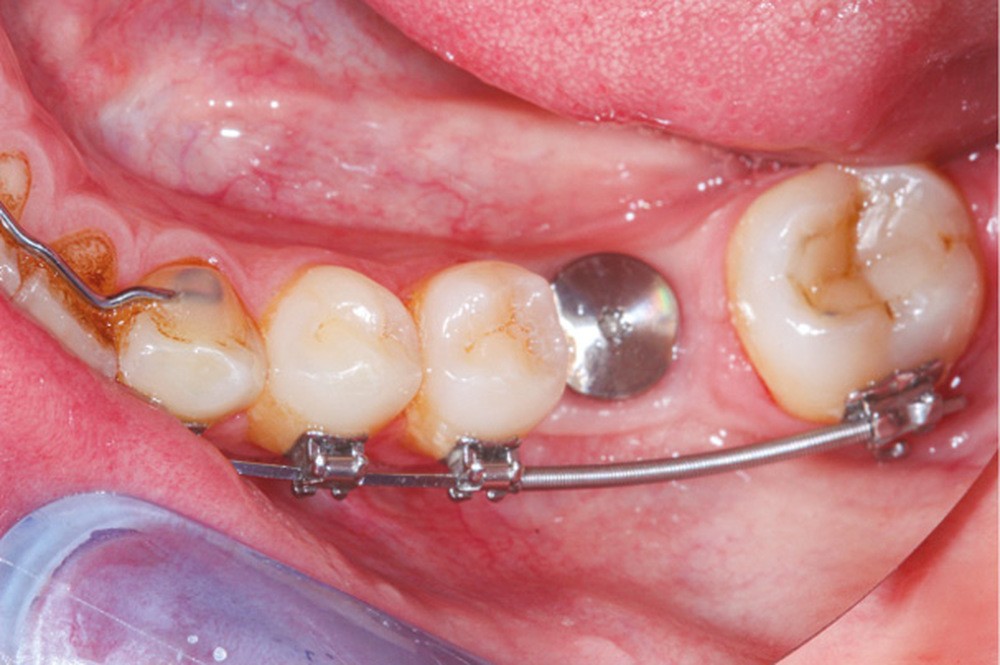

La prise en charge de ces édentements nécessite un examen complet du site implantaire et de l’environnement [16]. Les conséquences du non-remplacement rapide que nous venons d’énumérer sont à prendre en compte et à corriger pour une intégration optimale de la restauration prothétique implantaire. Ainsi, des corrections orthodontiques peuvent être nécessaires avant ou pendant la thérapeutique implantaire.

Le temps de l’ostéointégration, des versions ou migrations sont aussi possibles et le recours à des dispositifs de maintien de l’espace peut se révéler indispensable (fig. 22 et 23).